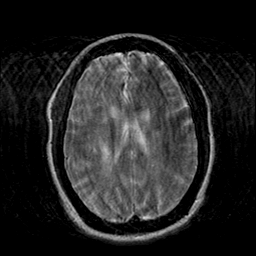

Cerebral hemorrhage, MR Study mr-t2 -- Slice #15

[Home][Help][Clinical] Slice 15